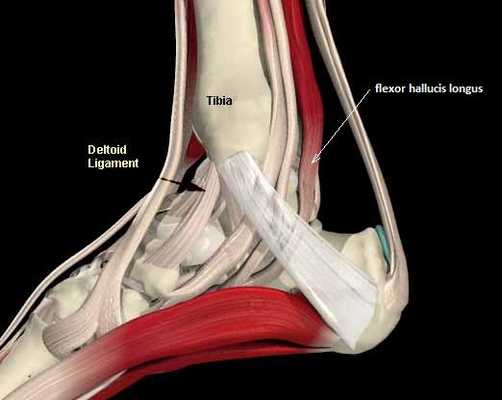

Повреждения сухожилия сгибателя большого пальца стопы распространённый вид травмы в таких группах риска как танцоры (прежде всего балета), гимнасты и скалолазы. Эти группы людей объединяет существенная перегрузка сгибателя большого пальца стопы при выполнении толчков и зацепов, стояния на пуантах. Вторым названием данной патологии является «тендинит танцора». В остальной популяции данные повреждения встречаются крайне редко. Так как сухожилие длинного сгибателя большого пальца проходит в фиброзно-костном канале позади внутренней лодыжки и голеностопного сустава, оно оказывается как бы перекинутым через задний отросток таранной кости, как верёвка перекинутая через блок.

Для хорошей визуализации рекомендуется использование жгута. Выполняется полукруглый разрез параллельно заднему краю внутренней лодыжки. Необходимо аккуратно выделить сосудисто-нервный пучок и взять его на держалку. Доступ к сухожильному каналу можно осуществить как спереди так и сзади по отношению к пучку. На этом этапе возможно выделение сухожилия, после его тщательного осмотра и пальпации, удаляются все узлы, спайки. При обнаружении треугольной кости необходимо её удалить.